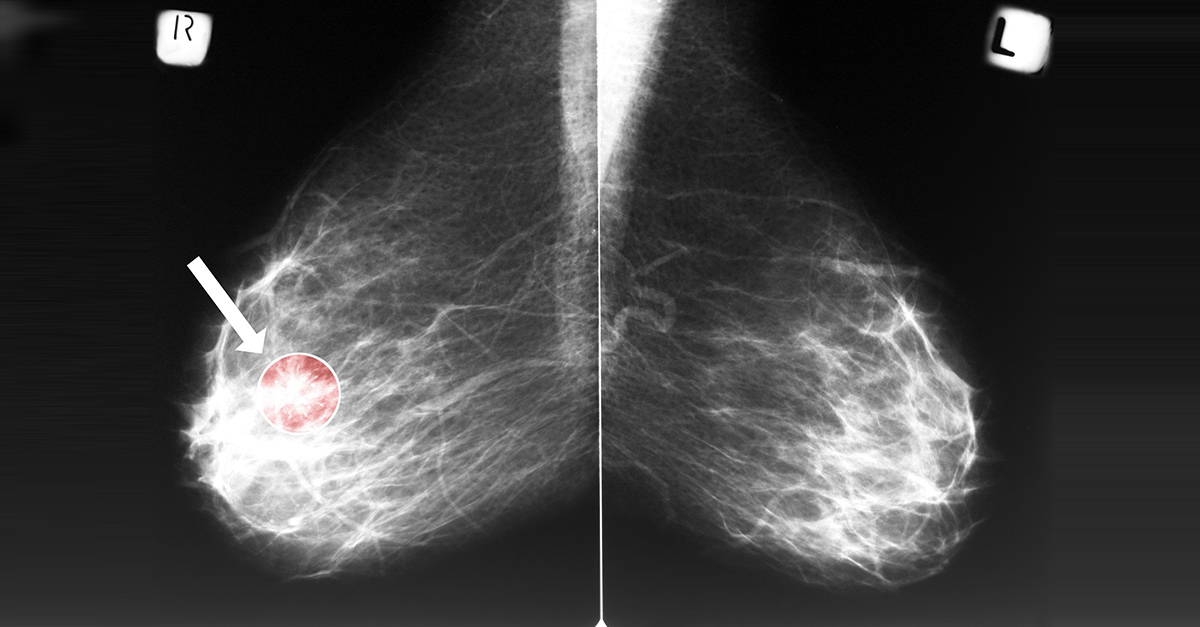

Surviving breast cancer is one thing. Recurrence, however, is a totally different ballgame. It’s something no one wants to face, but the chances are high during the first 2 years after treatment. Is it possible to stop a ruthless return?

Fortunately, it is. The risk of recurrence is never zero, but certain habits will keep it at bay. When breast cancer comes back, it may be in the same or opposite breast. Other times, it might even show up in a different part of the body. This can take months or years.1 2

Of all the breast cancer types, human epidermal growth factor receptor 2 (HER2) breast cancers are most likely to recur. But why risk it? Regardless of the type of cancer you have, avoiding a recurrence is always worth it. Here are the things you can do to prevent breast cancer recurrence.3